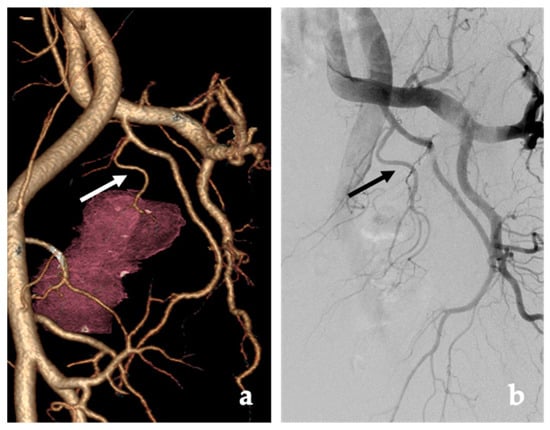

4.2. Procedure